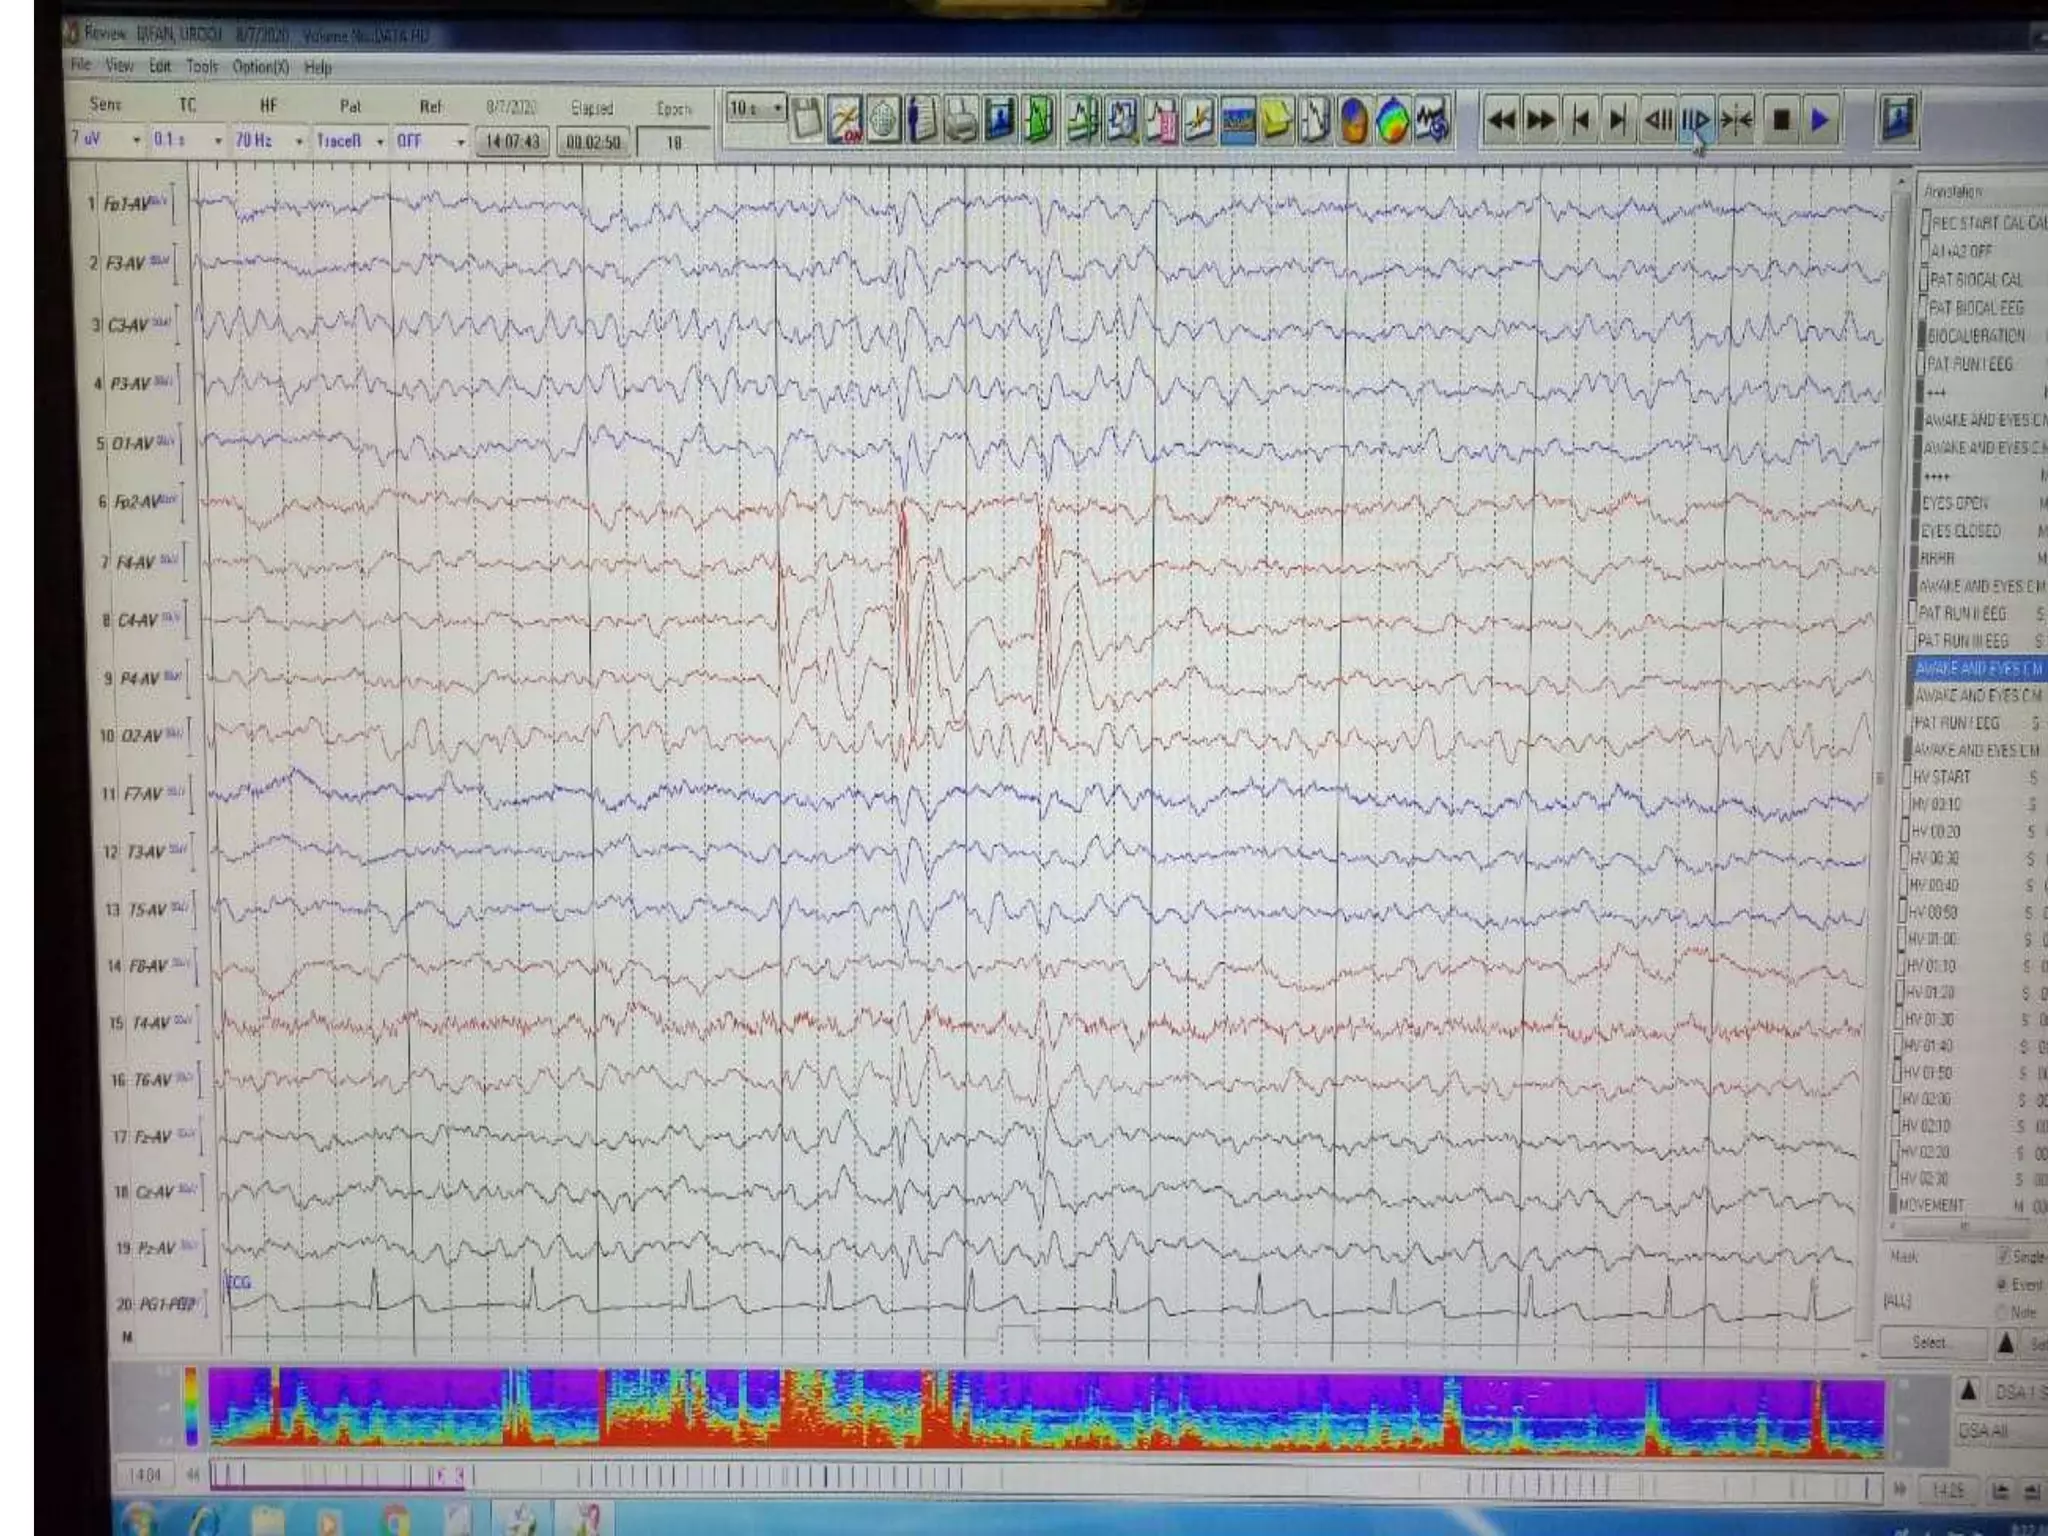

RIGHT SIDE IS SUPPRESED THAN LEFT AS PATIEN HAS HISTORY OF RIGHT MCA

RIGHT SIDE ISSUPPRESED THAN LEFT AS PATIEN HAS HISTORY OF RIGHT MCA INFARCT ‘